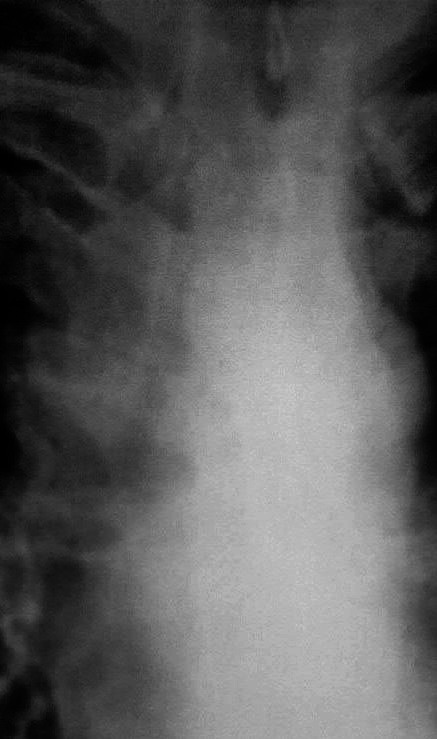

Потупил с диагнозом инфильтр tbs с поражением в/гр и периферич л/у. Болеет около месяца. Не контактен, пов t до 38. Менингиальные знаки 3+. Умер через 30 часов, на вскрытии...

Заподозрить еще как можно. Доказать, проблемно. Но подняв литературу узнал что картина типична для хронического... на фоне которого развивается... Обратите внимание на кисты слева, а справа формируется аналогичная.

Совершенно верно! Имеет место хронический лейкоз на фоне которого пневмония с распадом, кисты справа следствие таких же пневмоний. Остается вопрос почему кровь не набрали с самого начала.

Возраст около 45, точно не помню. На снимках еще стоял. Пока все мимо. Напомню увеличены в/гр и периферические л/у.

Неет причина смерти совсем иная. Уточню тут две патологии, одна обуславливает другую.